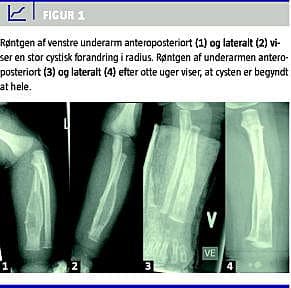

Et seks uger gammelt, i øvrigt raskt barn blev henvist med en tilsyneladende smertende og palpatorisk øm hævelse af venstre underarm. Røntgen viste en større osteolytisk forandring af venstre radius, der udgjorde cirka halvdelen af knoglens længde og med stedvis fordobling af knoglens diameter (Figur 1 ). Det histologiske billede fra en åben biopsi af venstre radius viste eosinofilt granulom. På baggrund af den usædvanligt lave debutalder blev patienten behandlet med kombinationsterapi i form af prednisolon samt vinblastin i seks måneder. En fuldkropsrøntgenskanning på diagnosetidspunktet viste ingen tegn på dissemineret sygdom, og opfølgende røntgenbilleder af venstre underarm viste tendens til regression af forandringerne i venstre radius (Figur 1).